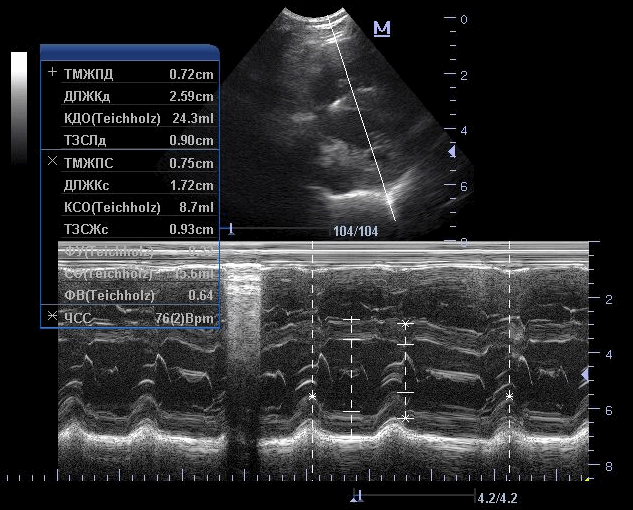

УЗИ сердца проводится в трех режимах: В-режим; М-режим и режим допплера. В-режим, или режим двухмерной ультразвуковой кардиографии, позволяет получить поперечные изображения сердца и магистральных сосудов в реальном масштабе времени и отличить полости сердца, заполненные кровью, от мягких тканей его камер, створок клапанов и сосудов. М-режим ультразвуковой кардиографии позволяет провести количественный анализ объема и движения камер сердца и клапанов. Режим допплера дает информацию о динамике потока крови и сосудах через камеры и клапаны сердца.

Рис.3. Эхокардиография. М-режим. Измерения параметров